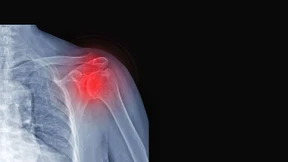

Quälende Schmerzen, diffuse Symptome und ein langer Weg zur richtigen Diagnose: Warum es so schwer ist, Rheuma frühzeitig zu erkennen, welche Warnsignale typisch sind und wie ein gesunder Lebensstil den Verlauf beeinflussen kann.

Arthrose ist eine schmerzhafte Angelegenheit, von der um die fünf Millionen Deutsche betroffen sind. Was man bei moderatem Knorpelabbau tun kann und wann eine Prothese notwendig ist, erfahren Sie im Podcast.